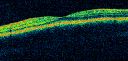

OCT SCAN: The OCT scans are normal.